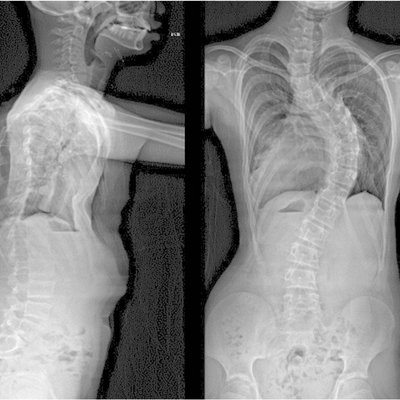

Click on an image below to view more info.